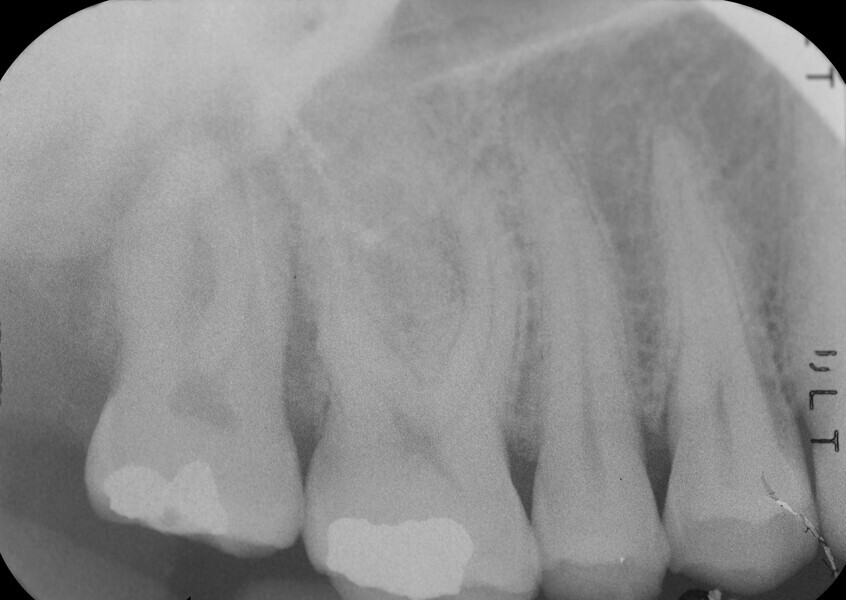

Fig. 3: Pre-op periapical radiograph.